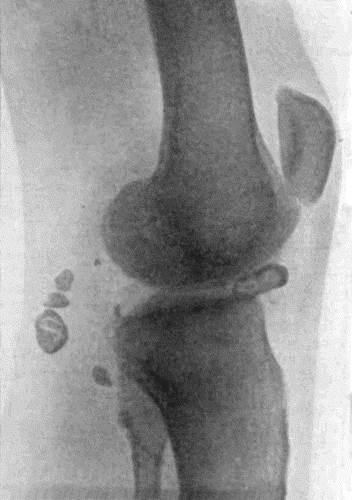

| 155. | Osseous Ankylosis of Knee | 504 |

| 162. | Bones of Knee in Charcot's Disease | 533 |

| 163. | Charcot's Disease of Left Knee | 534 |